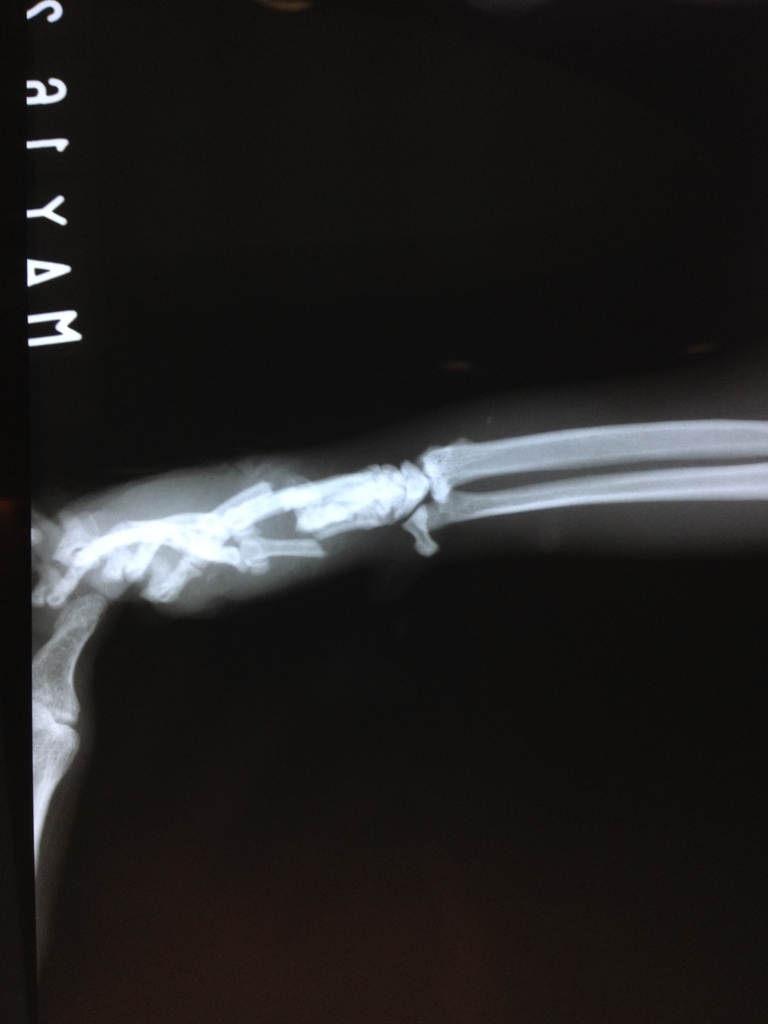

醫師診斷後發現他右前手異常腫脹,傷口滲血,且軟軟無力,懷疑是骨折,照X光後證實是掌骨斷裂,X光清楚可見3根掌骨斷裂並挫開交疊,判斷車壓過所致。

手術打入骨釘治療,打入3根最小號骨釘,街合支撐3根掌骨斷裂處,另進行牙齒檢查,5.16當天發現的牙齦化膿處拔除牙齒,以治療廔管發炎。